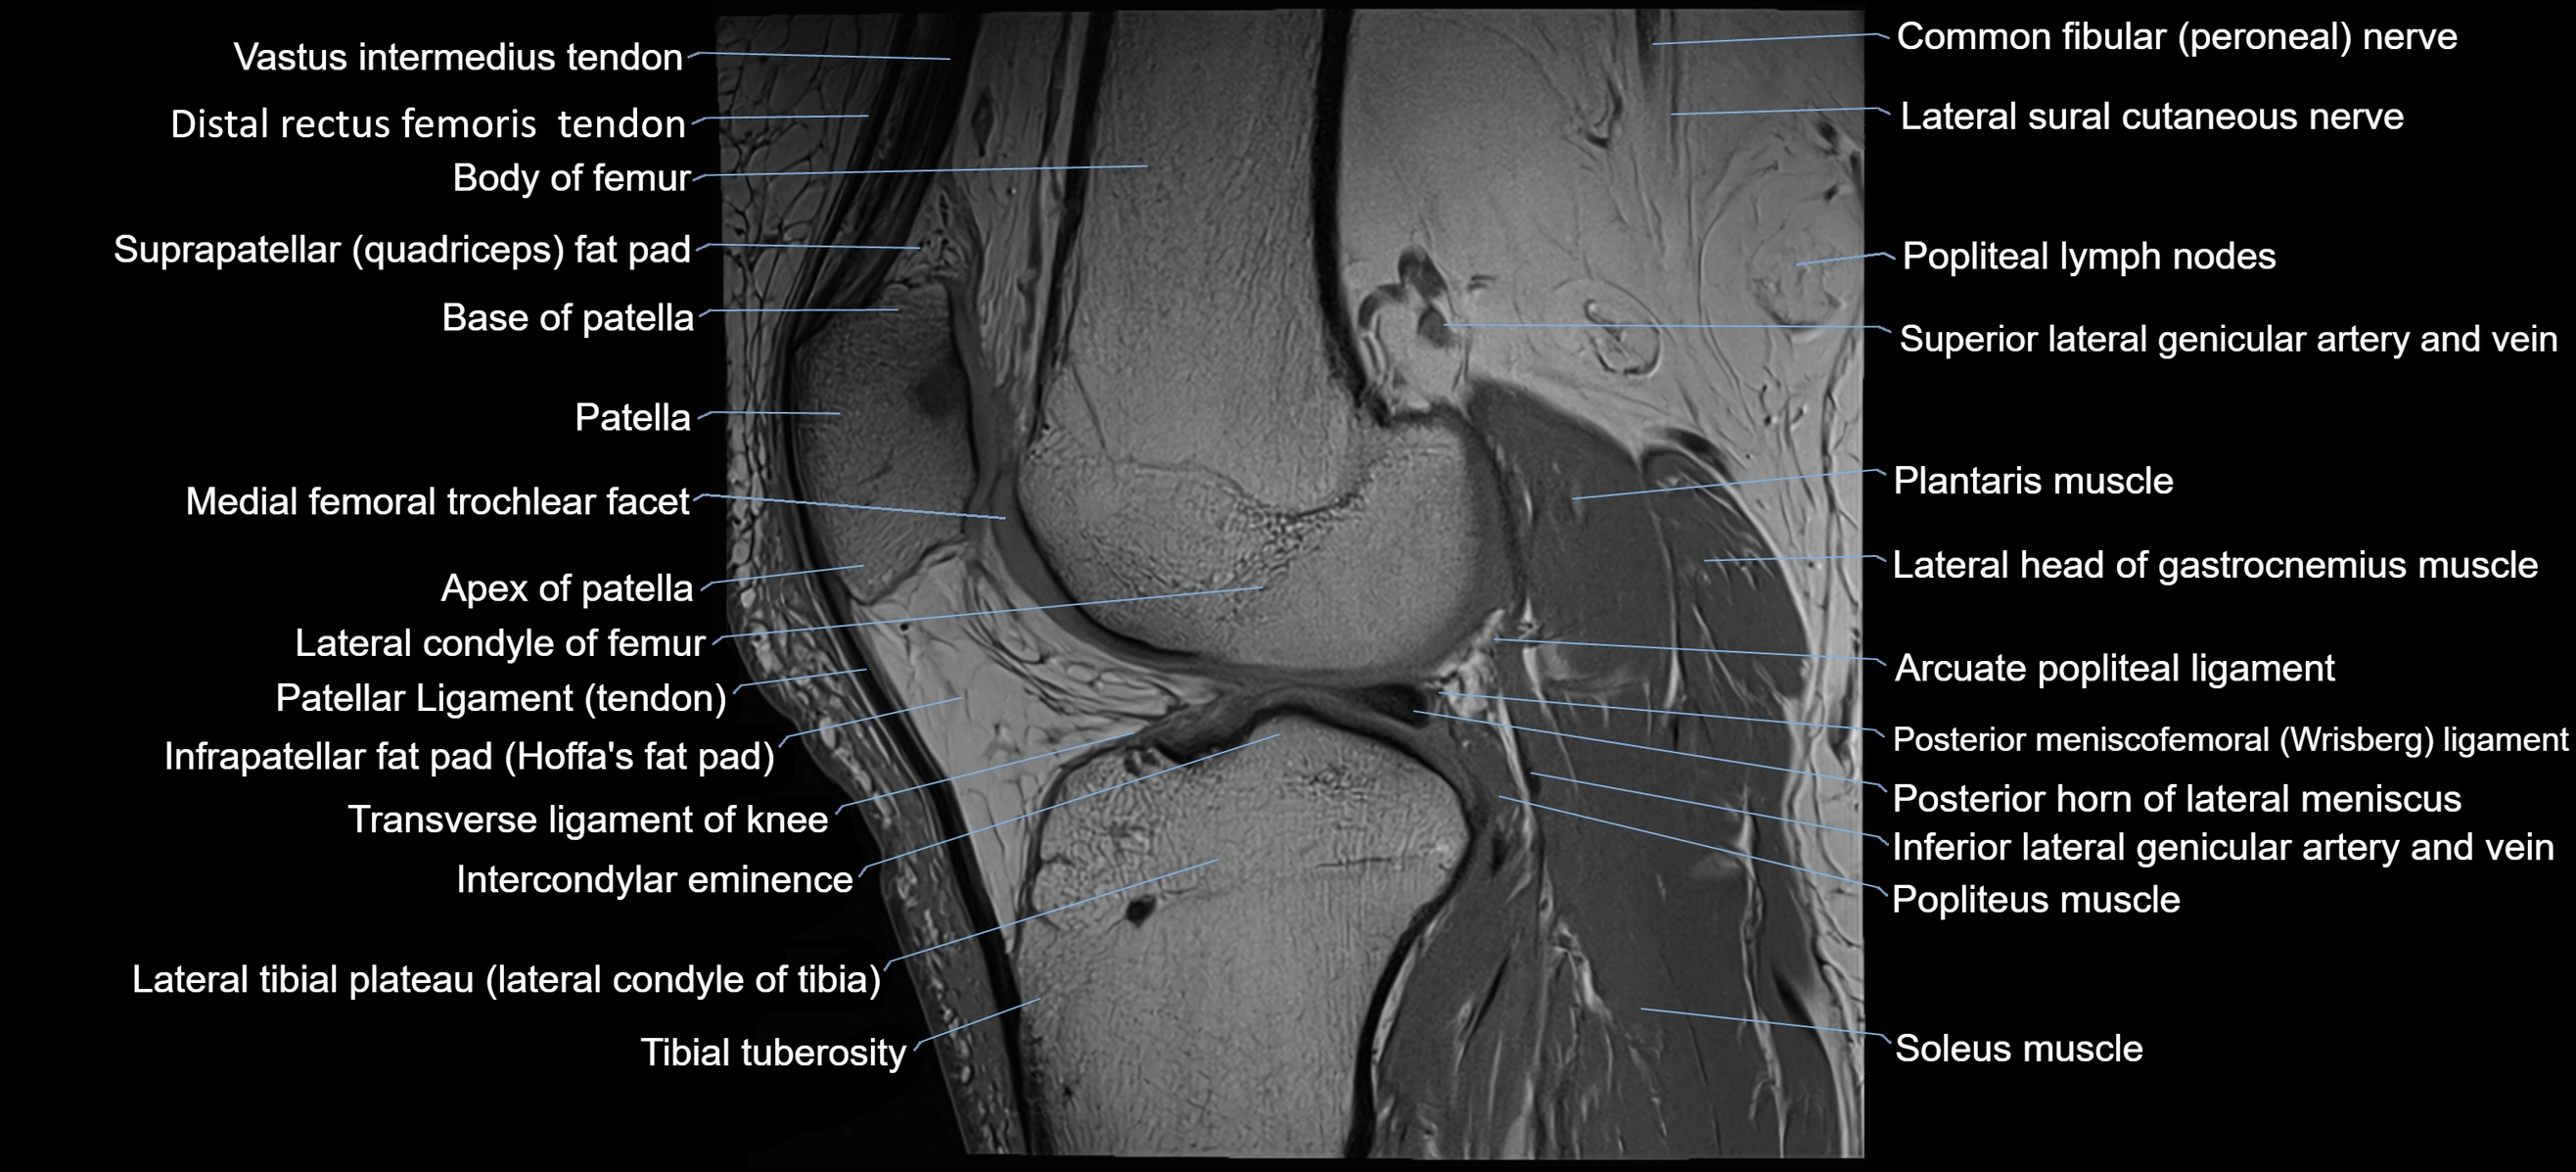

- Arcuate popliteal ligament

- Base of patella

- Body of femur

- Common fibular nerve

- Infrapatellar fat pad

- Intercondylar eminence

- Lateral condyle of femur

- Lateral head of gastrocnemius muscle

- Lateral sural cutaneous nerve

- Patella

- Patellar tendon (patellar ligament)

- Plantaris muscle

- Popliteal lymph nodes

- Popliteus muscle

- Posterior horn of lateral meniscus

- Posterior meniscofemoral ligament

- Soleus muscle

- Superior lateral genicular artery

- Suprapatellar fat pad

- Tibial tuberosity

- Transverse ligament of knee